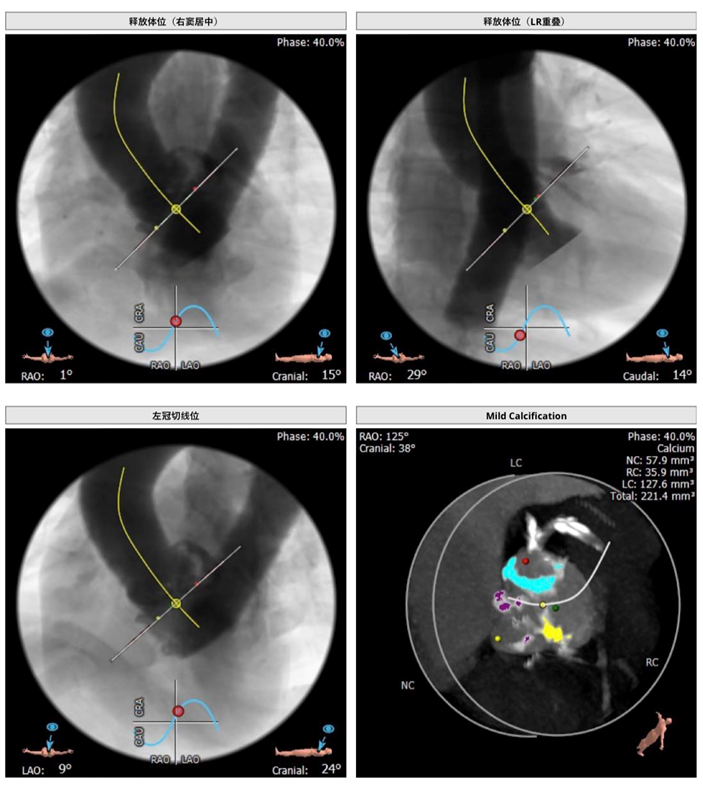

主动脉根部解剖CT影像

钙化积分:221.4mm³。